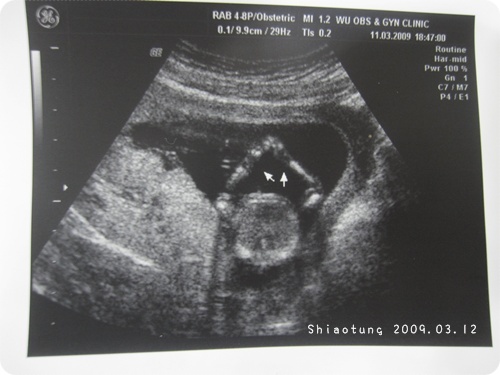

因此這回超音波,

有特地給我一張手和一張腳的照片,

下面照片是屁股往上拍。

沒記錯兩邊小圈是腳,

上面一個灰灰小影是頭在動來動去!

可以對照影片裡的部分。